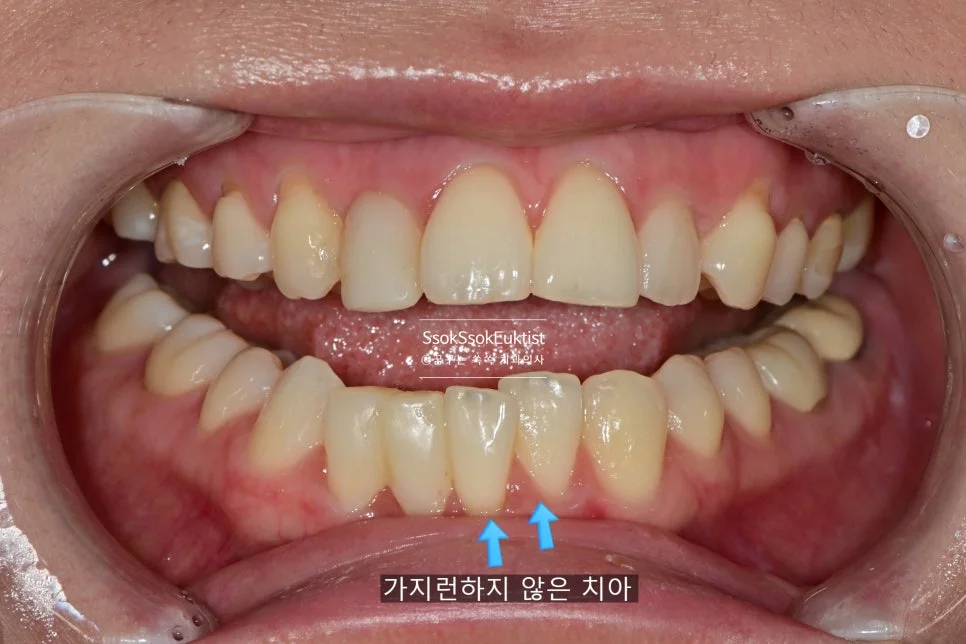

하악 교합면 사진 — 가장 전방에 위치한 치아 (화살표)

아래 앞니를 더 앞으로 뺄 필요는 없는 상황이었기에 라미네이트가 적합하지 않습니다!

가지런하지 않은 아래 앞니 (화살표) — 크라운 치료가 필요한 상태

모양과 위치를 드라마틱하게 개선하기 위해서는 크라운 치료가 필요하였고, 두 개 치아의 크라운 치료를 계획합니다. 그것도 신경치료 없이!!